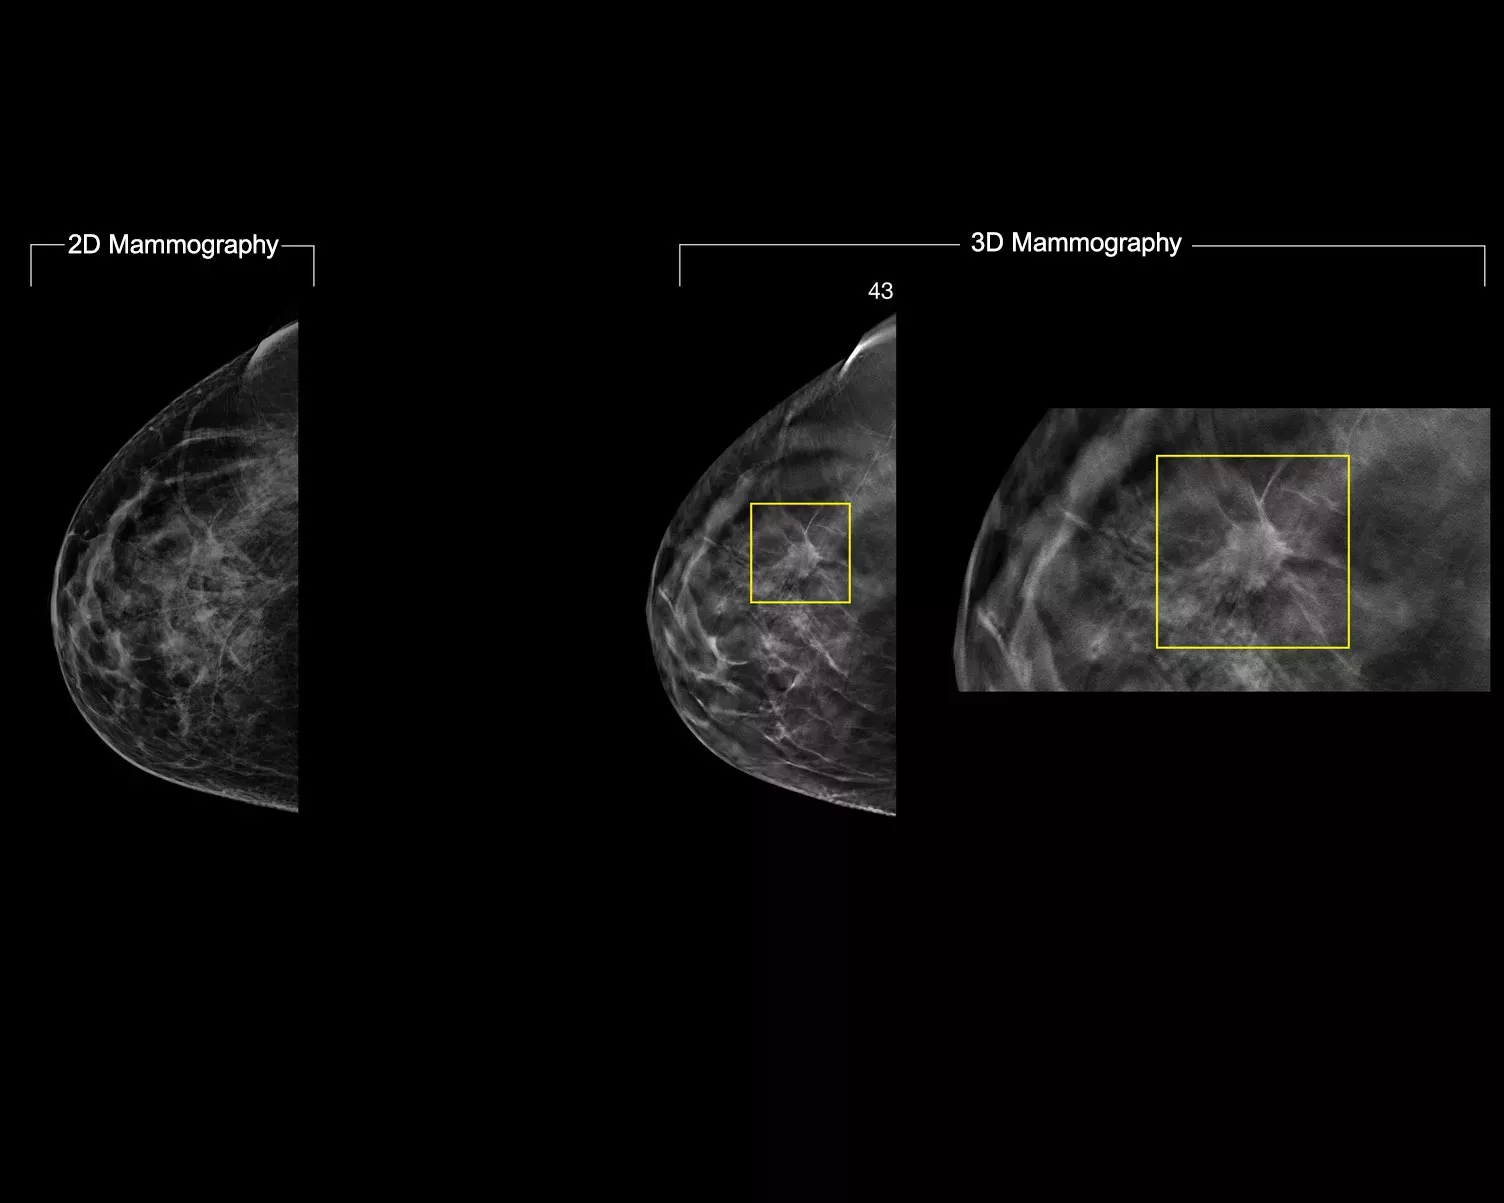

A deep-learning algorithm designed to aid radiologists' diagnostic performance of detecting breast cancer1-3 from tomosynthesis images obtained by using the Hologic Dimensions Mammography® Systems. The algorithm locates lesions that are likely to represent breast cancer by searching each slice of the tomosynthesis image set. The suspicious areas are highlighted for concurrent reading at the radiologist's workstation to aid in interpretation.

Study shows +9% improvement in observed reader sensitivity for cancer cases.1.2 Works on standard and high-resolution tomosynthesis images; overlay on 3DQuorum SmartSlices and synthesised 2D images.